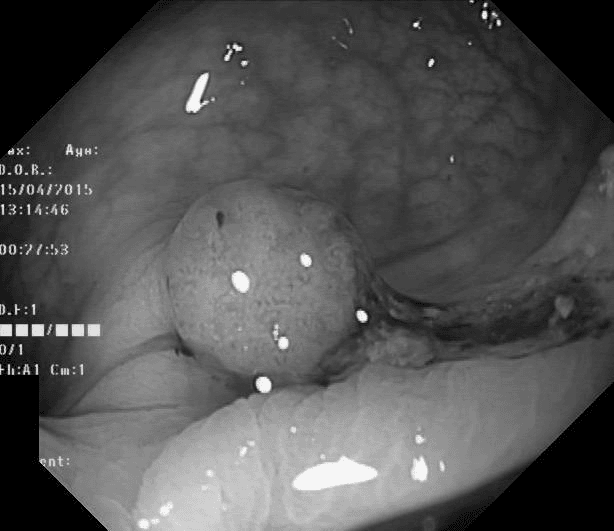

Refer to caption

(a) No abnormality

(b) Polyp

(c) Oesophagitis

(d) Ulcerative Colitis

Figure 1: Illustrations of question-answer pairs along with common abnormalities in gastrointestinal image from ImageCLEFmed-MEDVQA-GI-2023 dataset

The new dataset released for the ImageCLEFmed-MEDVQA-GI-2023 challenge is based on the HyperKvasir dataset [29], the largest gastrointestinal collections with more than 100,000 images, with the additional question-and-answer ground truth developed by medical collaborators. The development set and test set include a total of 3949 images from different procedures such as gastroscopy and colonoscopy, spanning the entire gastrointestinal tract, from mouth to anus. Each image has a total of 18 questions about abnormalities, surgical instruments, normal findings and other artefacts, with multiple answers possible for each, as shown in Table 1. Not all questions will be relevant to the provided image, and the VQA system should be able to handle cases where there is no correct answer. Figure 1 depicts several examples of question-answer pairs on common abnormalities in gastrointestinal tract, such as Colon Polyps, Oesophagitis, and Ulcerative Colitis. As shown in Figure 1(d), there are three possible answers to the question "What color is the abnormality?": "Pink," "Red," and "White", and a typical VQA system should be able to identify all three colors. In general, the image may contains a variety of noise and components that locates across abnormalities, such as highlight spots or instruments, which pose a significant challenge in developing efficient VQA systems for gastrointestinal domain.